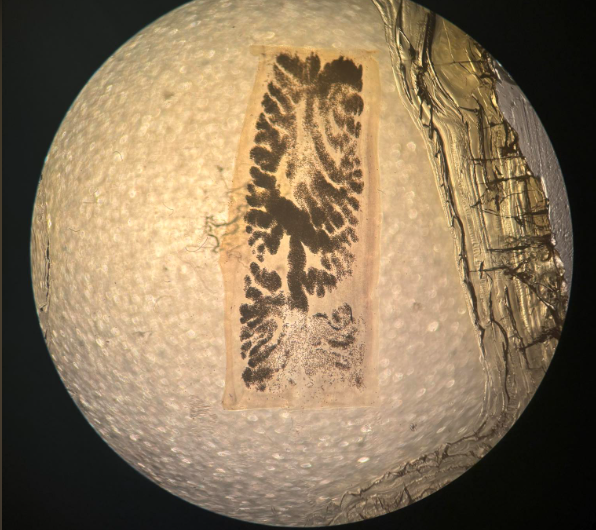

taenia saginata proglotyd przejrzały

taenia solium proglotyd przejrzały